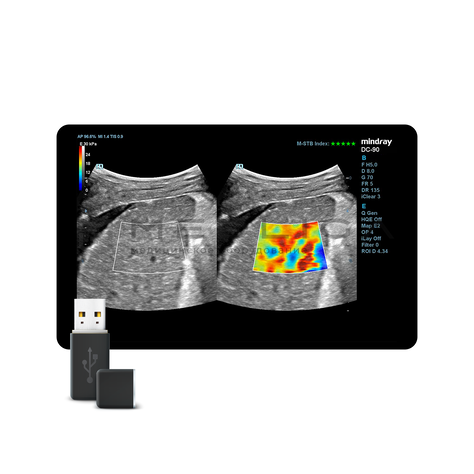

Программное обеспечение для оценки эластичности ткани методом эластографии сдвиговой волны (метод 2D-с формированием двухмерной цветовой эластограммы и количественной оценкой эластичности) на линейных и конвексных датчиках.

STE интегрирована с эксклюзивной технологией Ultra-Wide Beam Tracking от Mindray для двумерной эластографии сдвиговой волной в реальном времени. Специализированные измерительные инструменты позволяют проводить количественный анализ модуля упругости с высокой точностью.

Опция работает:

• на линейных датчиках

• на конвексных датчиках